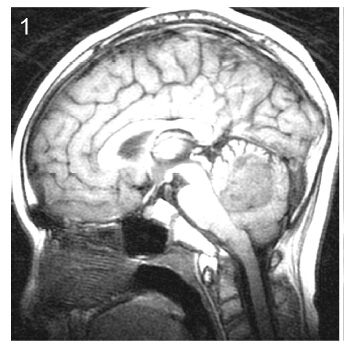

2 Patients and methods This study was approved by Ethics Committee of Tiantan Hospital, Capital Medical University. We retrospectively reviewed the medical records of all patients operated at our hospital between January 2004 and January 2007 who were diagnosed with medulloblastoma and were aged 16 years or older at diagnosis. Follow-up data were collected by telephone or follow-up visits at the clinic.Tumor location was defined as central or lateral on the basis of preoperative computed tomography and magnetic resonance neuroimaging findings and surgical reports (Figures 1-3). Because infiltration of the floor of the fourth ventricle was only observed in cases of centrally located tumors, we classified the tumors into three subtypes: those located at the midline without infiltration of the fourth ventricle floor, those located at the midline with infiltration of the fourth ventricle floor, and those located laterally.

| Figure 3 Subtype 3, laterally located tumor. |